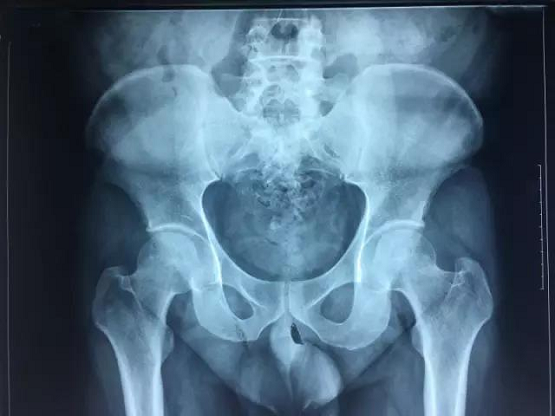

上图为适合汤剂治疗的病例

目前市面上治疗股骨头坏死的单方中成药,在治疗这一复杂的慢性疾病时,就会显得单薄许多,比如在镇痛方面,就不如复方。在临床中,很多患者服用单味中成药,疼痛很难得到有效控制,容易导致患者自己去服用激素类止痛药,导致病情越来越重,恶性循环,加大了保髋难度。